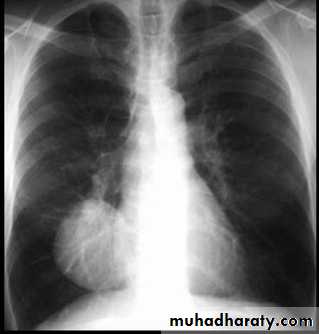

Massive pleural effusion with mediastinal shift to the left.

(A) Chest radiograph

(B) CT coronal reconstruction. A massive effusion displaces the mediastinum to the left. CT shows the important pleural effusion together with the enhanced atelectatic left lung.

Note also the depression of the right hemidiaphragm (arrows).